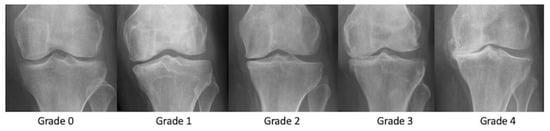

3.1. Radiographs

- Slattery, C.; Kweon, C.Y. Classifications in Brief: Outerbridge Classification of Chondral Lesions. Clin. Orthop. Relat. Res. 2018, 476, 2101–2104. [Google Scholar] [CrossRef]